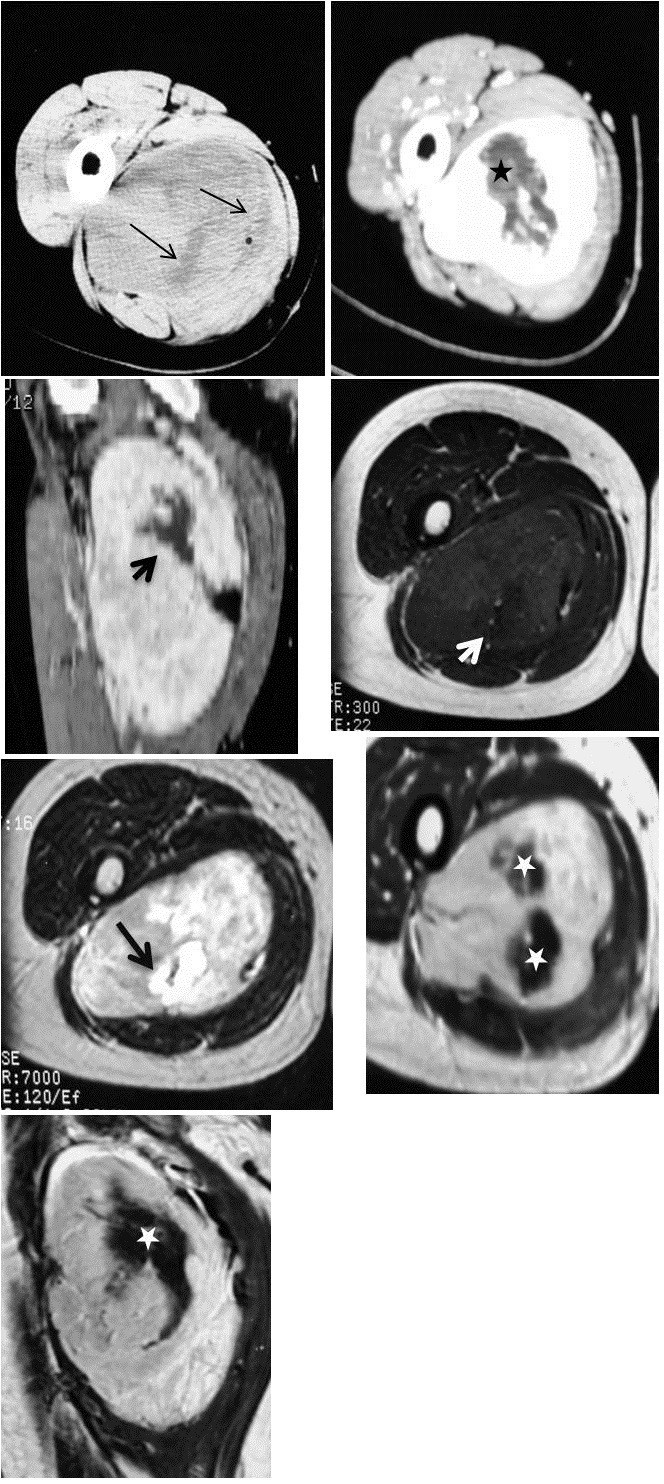

Of the eighteen lesions imaged with CT scan, five were hypodense (Figure 1) and two were isodense (Figure 2A) to adjacent musculature while eleven lesions appeared heterogeneous-mixed of iso and hypodense areas, on 1pre-contrast exams (Figures 3A, 4B). Attenuation values of the lesions were also higher than subcutaneous fat. Heterogeneous enhancement was evident in thirteen lesions while homogeneous contrast uptake was observed in four lesions (Figures 1B, 2C) (one case had no contrast administration). Septations were exhibited only in one CT case. All of the heterogeneously enhanced tumors contained markedly hyperdense portions admixed with patchy hypodense areas with mild to no enhancement (Figures 3B, 3C, 4C). In the dynamically –enhanced CT case, mild heterogeneous contrast uptake was depicted at 30 s and more intense prolonged enhancement was shown at 90 s and 180 s respectively (Figures 2B, 2C).

Unenhanced CT scan (A) displays a deep soft tissue mass with internal calcifications lying adjacent to the diaphysis of the left radius. The mass exhibits slightly lower attenuation compared to the neighboring muscles (black arrow). On contrast CT scan (B), the mass is homogeneously enhanced (white arrow). Ultrasound (C) demonstrates a hypoechoic mass containing multiple calcifications.

Unenhanced CT (A) demonstrates a deep soft tissue mass in the left paravertebral area (asterisk). The mass is isodense compared to muscle. No bone erosion is observed. At 30 s post-contrast infusion (B) the lesion exhibits mild heterogeneous enhancement while at 90 s post-contrast infusion (C) the lesion shows more intense homogeneous and prolonged enhancement.

Unenhanced CT scan (A) demonstrates a well-defined heterogeneous deep soft tissue mass containing scattered hypodense areas ( thin arrows). Enhanced CTimages (B–C) display heterogeneous enhancement. MR T1W image (D) displays an isointense mass relative to adjacent muscle containing an area of relative lower intensity (white arrow) that has markedly high SI on T2W MR image (E) (black thick arrow). Heterogeneous enhancement is depicted on enhanced T1MR images (F–G). Central unenhanced areas (asterisks) on both CT and MRI exams were of low SI on MRT1W images and high SI on T2W MR image.

A total of fourteen cases were examined with MR imaging. On T1WSE, seven lesions were isointense to surrounding muscles (Figure 5A), one was hyperintense and five lesions were heterogeneous-mixed of iso and hypointense areas (Figure 3D). All lesions exhibited lower T1W signal intensity than subcutaneous fat. Of the nine tumors examined with T2WSE, seven lesions demonstrated mixed intensities with hyper and hypointense areas (Figure 3E) and two lesions were hyperintense (Figure 5B). Nine lesions failed to suppress and presented with heterogeneous/mixed intensities on T2 FSE fat sat and STIR images. Post-gadolinium exams revealed homogeneous and heterogeneous enhancement in four (Figure 5C) and six cases (Figures 3F, 3G) respectively. Patchy unenhanced areas were evident in six out of ten enhanced cases while irregularly shaped areas of low to markedly high signal intensities were additionally observed on T2WSE images of the four cases that were not imaged with gadolinium. Septations were noticed in eight MRI exams (Figures 5B, 5C). In total, patchy areas with mild or no enhancement on CT and T1WSE images and areas of low to markedly high signal intensities on T2WSE were observed in 19 (70,3%) out of 27 cases.

A deep soft tissue mass is intramuscularly located at the right gluteus maximus muscle (white arrow). The mass is isointense relative to adjacent muscle on T1 MR images (A). The mass has high SI and contains septations on T2MR image (B: white arrowhead). On gadolinium –enhanced T1 images (C), the lesion displays marked homogeneous enhancement. Internal septations remain unenhanced.

Radiological findings concerned twenty seven well-defined masses with round or ovoid shapes displacing adjacent anatomic structures. On unenhanced CT images, pleural SFTs appeared isodense relative to muscle and some contained hypodense areas, while on enhanced CT images they usually exhibited mild to marked heterogeneous contrast uptake [35, 36]. According to the Rosado-de-Christenson et al. study [36], isodensity on pre contrast CT scans correlates with hypercellular areas and capillary networks while markedly enhanced regions represent hypervascular areas, intermediate enhanced areas correlate with hypocellularity, and patchy hypodensities correspond to necrotic, myxoid or cystic changes. Of our eighteen lesions imaged with CT scans, two were isodense, five appeared relatively hypodense compared to neighboring muscles and eleven were mixed of isodense and hypodense areas. On enhanced images thirteen lesions were markedly and heterogeneously enhanced including patchy unenhanced areas (Figures 3B, 3C, 4C) while only four exhibited a more homogeneous enhancement pattern (Figures 1B, 2C). In reference to the dynamic characteristics, Fuksbrumer et al. [12] and Moser et al. [13] stressed the importance of marked and delayed enhancement and washout in characterizing liver SFTs. In our study, one case (Figure 1B) that was assessed with dynamic CT protocols, presented with mild arterial enhancement and more intense and prolonged enhancement on late venous and delayed phases. These features related histologically to cellular areas (prolonged enhancement) admixed with collagenous stroma (delayed enhancement).

According to the published MR features of SFTs, isointensity to muscle is most commonly displayed on T1-weighted sequences along with an increase of signal intensity on post gadolinium images and variable appearance on T2-weighted sequences. It is considered that the variety of signal intensity on T2-weighted images depends upon the different nature of the tumor components, namely, the amount of collagen and cellularity (fibroblasts), and on the presence of degeneration [9, 34]. This series included seven masses of equal signal intensity on T1-weighted images relative to muscle (Figure 5A) and five lesions of heterogeneous-mixed intensity (Figure 3B, 3C). In most MR studies on mature fibrous tissue, the observed hypointensity on both T1 and T2-weighted sequences is related to the presence of hypocellularity and abundant collagenous stroma whereas fibrous tissue of relative increased cellularity and vascularity increases the signal intensity on T2-weighted sequences (Figure 5B) [34, 37, 38]. The aforementioned was noticed in all nine lesions that showed mixed to high signal intensities on T2-weighted images. Gadolinium enhancement of SFTs is generally a result of tumor vascularization that may vary from hypovascularity to hypervascularity. Of the ten cases that received gadolinium, six revealed intense heterogeneous enhancement and the remaining four cases were more homogeneously enhanced (Figure 5C). Similarly to the Tateishi et al. study [34], the enhancing portions corresponded histologically to areas of abundant cellularity combined with microvessels. Patchy heterogeneous areas of variable size were depicted in totally ten MRI exams (Figures 3F, 3G). Four of these cases demonstrated areas of low to intermediate and markedly high signal intensity on T2WSE and the remaining six showed areas of mild to no uptake on post contrast images and were correlated to hypocellular collagenous stroma (n=10) with co-existing necrotic (n=3) or degenerative (n=2) changes. Hypocellular collagenous stroma was also correlated with the patchy unenhanced areas of the remaining nine (n=9) contrast CT cases with co-existing necrotic changes in only one case (n=1). On histologic analysis there were additionally two other cases with necrotic changes; one of which was imaged solely with MRI and appeared homogeneous both on pre and post gadolinium images and the other was imaged only with U/S and contained a few scattered hypoechoic areas. Moreover, thin hypointense on T2WSE, linear or curvilinear structures were observed in eight out of fourteen MRI cases. These structures remained unenhanced and were attributed to smooth hypocellular fibrous septations. Calcifications are suggestive of necrosis but they are only sporadically reported in extrathoracic SFTs [17]. Likewise in this study, it was depicted in only six cases (22,2%).